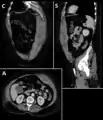

Rectus sheath hematoma seen on axial CT – with active bleeding under Marcoumar- Rectus sheath hematoma as seen on ultrasound[5]